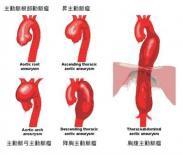

感染性腹主动脉瘤

628健康网为您分享有关感染性腹主动脉瘤的症状,感染性腹主动脉瘤的治疗方法,感染性腹主动脉瘤的预防知识,感染性腹主动脉...

锁骨下动脉-腋动脉瘤

628健康网为您分享有关锁骨下动脉-腋动脉瘤的症状,锁骨下动脉-腋动脉瘤的治疗方法,锁骨下动脉-腋动脉瘤的预防知识,锁骨下...

腹部大血管损伤

628健康网为您分享有关腹部大血管损伤的症状,腹部大血管损伤的治疗方法,腹部大血管损伤的预防知识,腹部大血管损伤的症状...

腹主动脉瘤

628健康网为您分享有关腹主动脉瘤的症状,腹主动脉瘤的治疗方法,腹主动脉瘤的预防知识,腹主动脉瘤的症状图片,腹主动脉瘤...

奈动脉瘤

628健康网为您分享有关奈动脉瘤的症状,奈动脉瘤的治疗方法,奈动脉瘤的预防知识,奈动脉瘤的症状图片,奈动脉瘤吃什么药,奈...